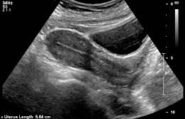

Laparoscopic fibroid removal is a minimally invasive procedure to remove uterinefibroids, benign (not cancerous) growths in a woman’s uterus. The procedure can help relieve uterine fibroid symptoms such as abnormally heavy menstrual bleeding, pain in the pelvic region, and pressure on the bladder or bowel.

A very large uterine fibroid can cause the uterus to expand to the size of a 6 or 7 month pregnancy. Fibroids can form as one single dominant fibroid or as a cluster of many small fibroids. Consequently there is more thickened lining to shed when during your period. … If your fibroids are big enough, you will feel a stronger sensation of pressure at the time of your period because of blood flow to the fibroidsFibroids put more pressure on the uterine lining, also causing more bleeding and pain.